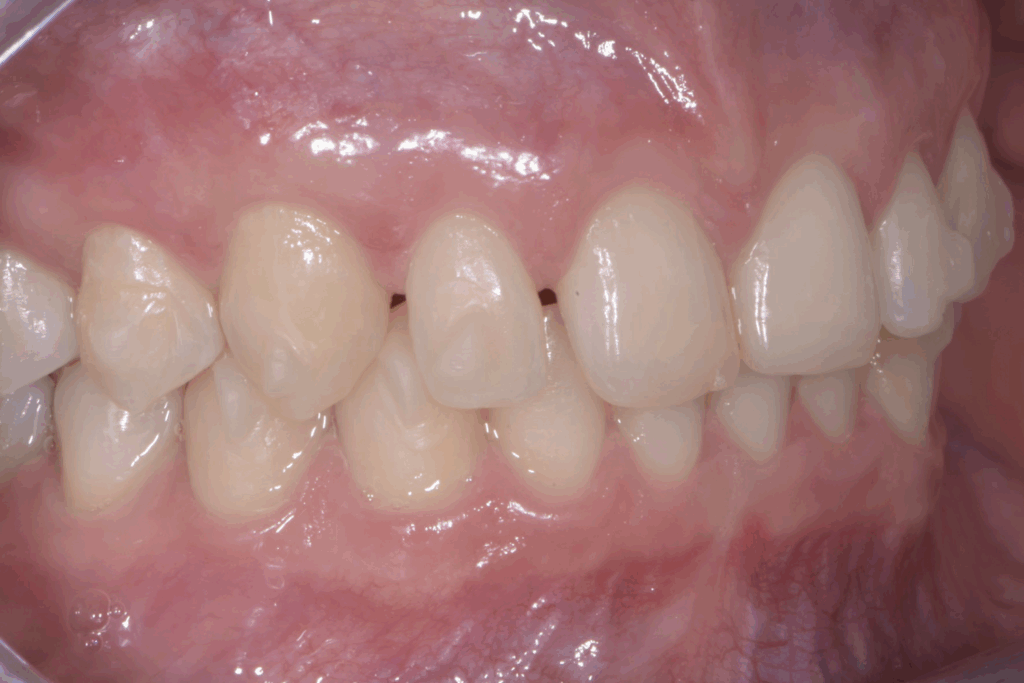

A 17 anni, una paziente si è rivolta al nostro studio con l’obiettivo di migliorare il proprio sorriso e la funzionalità masticatoria. Il caso clinico presentava una combinazione di problematiche comuni e complesse: agenesia dei settimi inferiori, incisivi superiori di piccole dimensioni e un morso profondo. Questa situazione non solo comprometteva l’estetica del sorriso, ma poteva causare problemi funzionali a lungo termine. La soluzione scelta per questa giovane paziente è stata un approccio combinato di ortodonzia moderna con allineatori trasparenti e odontoiatria estetica conservativa.

La prima fase del trattamento è stata un’analisi approfondita. Durante il check-up, abbiamo confermato la diagnosi di agenesia dei secondi molari permanenti inferiori, una condizione congenita che lascia spazi vuoti nell’arcata. Abbiamo inoltre rilevato che gli incisivi superiori erano di dimensioni ridotte rispetto al resto dei denti e che la paziente presentava un morso profondo, con gli incisivi superiori che coprivano eccessivamente quelli inferiori. Questa valutazione completa ci ha permesso di creare un piano di trattamento personalizzato e preciso, tenendo conto di tutte le problematiche presenti.

Per affrontare le sfide del caso, abbiamo optato per l’utilizzo di allineatori trasparenti. Questo tipo di trattamento è stato scelto per la sua efficacia nel muovere i denti in modo preciso e graduale, ma anche per la sua discrezione, fondamentale per una paziente in età scolare. Il piano di trattamento ha previsto una serie di allineatori personalizzati, che la paziente doveva sostituire con il passare delle settimane.

- Chiusura degli spazi: gli allineatori sono stati programmati per spostare i denti posteriori e chiudere gli spazi vuoti lasciati dall’agenesia dei settimi, evitando la necessità di impianti o ponti.

- Correzione della verticalità: il trattamento ha lavorato per estrusione e intrusione selettiva di alcuni denti, al fine di correggere il morso profondo e ristabilire una corretta occlusione.